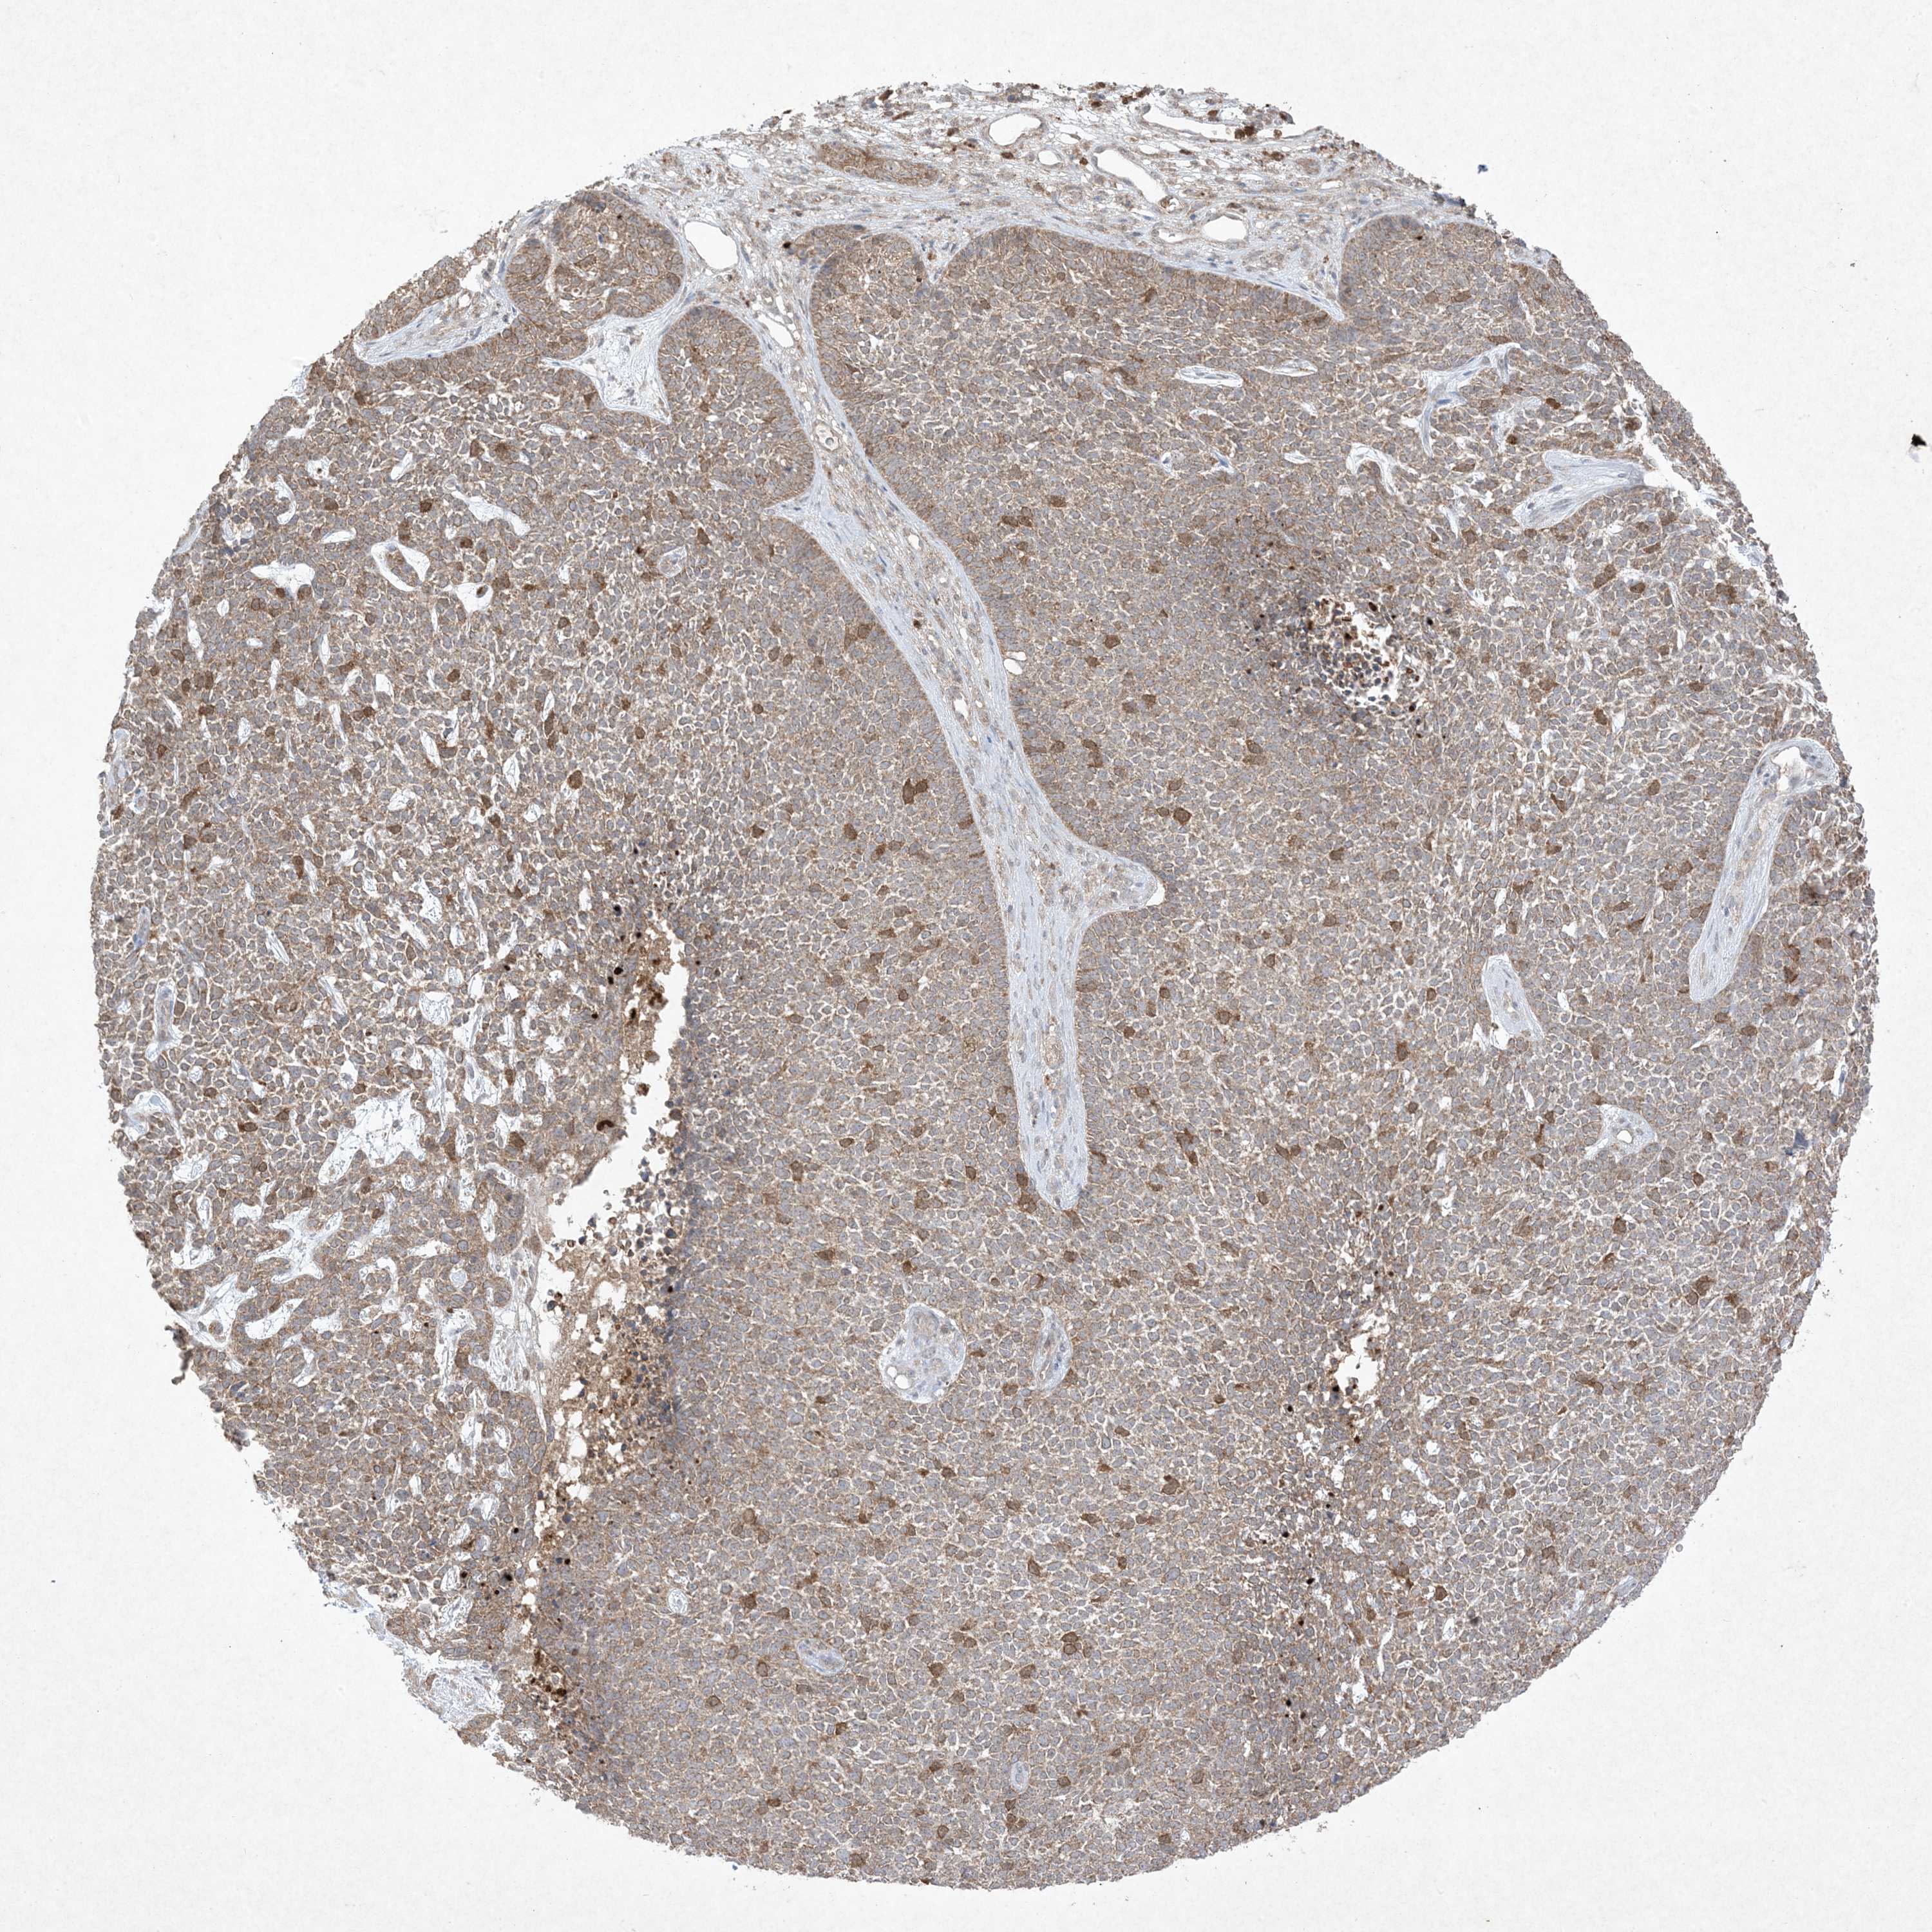

SKIN CANCER - Protein expressioni

A mouse-over function shows sample information and annotation data. Click on an image to view it in a full screen mode. Samples can be filtered based on level of antibody staining by selecting one or several of the following categories: high, medium, low and not detected. The assay and annotation is described here.

Each image is clickable and will lead to virtual microscopy that enables deeper exploration of all samples and also displays staining intensity scores, fraction scores and subcellular localization as well as patient and tissue information for each sample.

Antibody HPA054975

Antibody CAB011464

Antibody CAB035990

Antibody CAB080407

Staining

High

Medium

Low

Not detected

Intensity

Strong

Moderate

Weak

Negative

Quantity

>75%

75%-25%

<25%

None

Location

Nuclear

Cytoplasmic/membranous

Cytoplasmic/membranous,nuclear

Squamous cell carcinoma, NOS